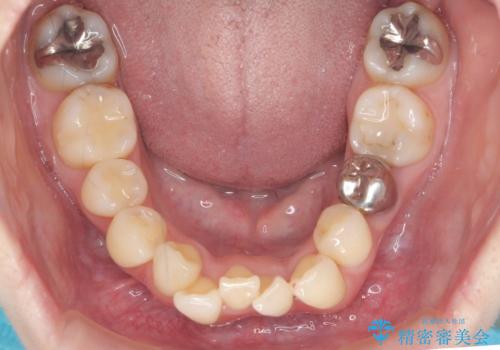

- 八重歯を主訴に来院。他院で全体ワイヤー矯正、4本抜歯で3-4年かかるかもしれないと説明を受けたとのこと。

八重歯の部分は抜歯し、奥に入っていた前歯を前に移動させました。

下の前歯は生まれつき3本だったため、さらに2本下を抜くとなると3本少なくなってしまうため、下の前歯を一本お取りして最小限の抜歯としました。

上にはワイヤー部分矯正を行った後、インビザラインでマウスピース矯正を行っています。